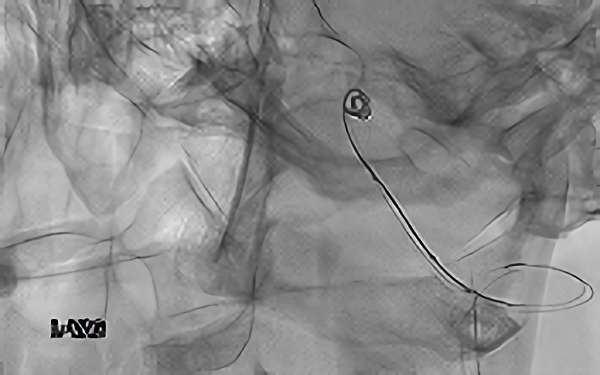

左椎骨動脈後下小脳動脈分岐部動脈瘤

70代

院内外来

No.1628 手術前

No.1628 手術中

No.1628 手術後